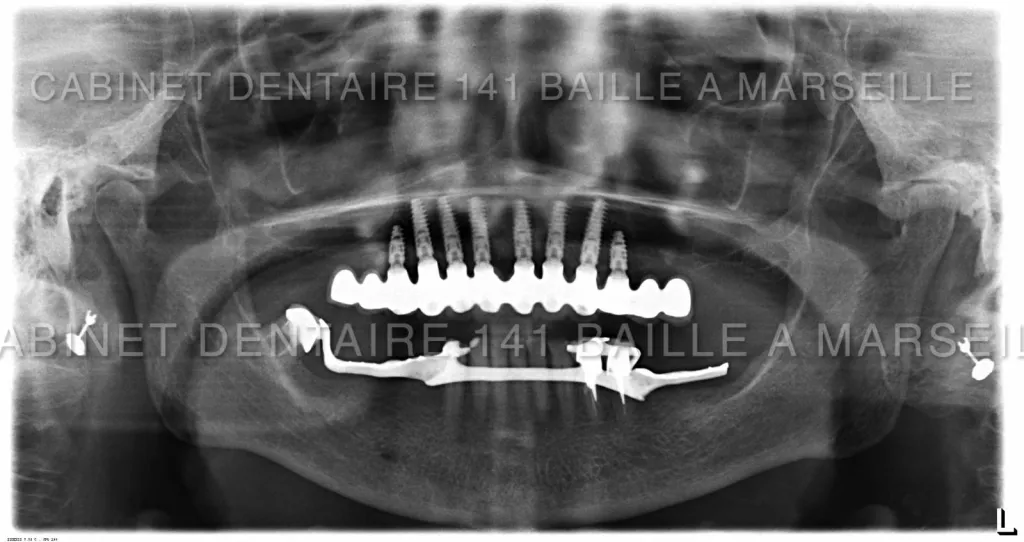

Il peut arriver qu'un patient soit obligé de remplacer toutes ses dents par des implants  dans certains cas de maladies de gencives très agressives qui entrainent une destruction de l'os support des dents .

De nos jours il est possible pour ces patients d'avoir recours à des techniques implantaires appelées implantation complète en général effectuées dans la meme journée .On appelle cette technique la technique d'implantation complète avec mise en charge immédiate (MCI).

Ces techniques necessitent toutefois un chirurgien implantologiste qualifié et formé à ces techniques de mise en charge immédiate,d'un plateau technique complet avec bloc opératoire stérile ,prothésiste,et personnel d'assistance chirurgical qualifié.